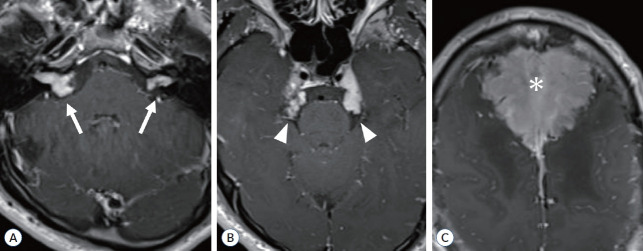

2型神经纤维瘤病(NF2)是一种常染色体显性遗传病,以双侧前庭神经鞘瘤和其他中枢神经肿瘤如脑膜瘤和脊髓室管膜瘤为特征。症状根据诊断时的年龄和肿瘤的位置而有所不同。NF2的诊断标准已定期修订,并于2022年更新了新的命名法“NF2相关神经鞘瘤病”,以区分NF2与其他神经鞘瘤易感性疾病,如SMARCB1-、LZTR1-和22q相关神经鞘瘤病。除了临床特征外,对这些基因的致病变异进行基因检测成为支持NF2和其他神经鞘瘤病(包括花叶病)诊断的重要本质。

Neurofibromatosis type 2 (NF2) is an autosomal dominant disease characterized by bilateral vestibular schwannomas and other central nervous tumors such as meningiomas and spinal ependymomas. Symptoms vary according to the age at diagnosis and the location of these tumors. The diagnostic criteria of NF2 have been regularly revised and recently updated in 2022 with a new nomenclature "NF2-related schwannomatosis" to differentiate NF2 from other schwannoma predisposing disorders, such as SMARCB1 (SWI/SNF-related, matrix-associated, actin-dependent regulator of chromatin, subfamily b, member 1)-, LZTR1 (leucine zipper-like transcription regulator 1)-, and 22q-related schwannomatosis. Addition to the clinical features, genetic testing for pathogenic variants in these genes became an important essence to support diagnosis of NF2 and other schwannomatosis, including mosaic conditions.